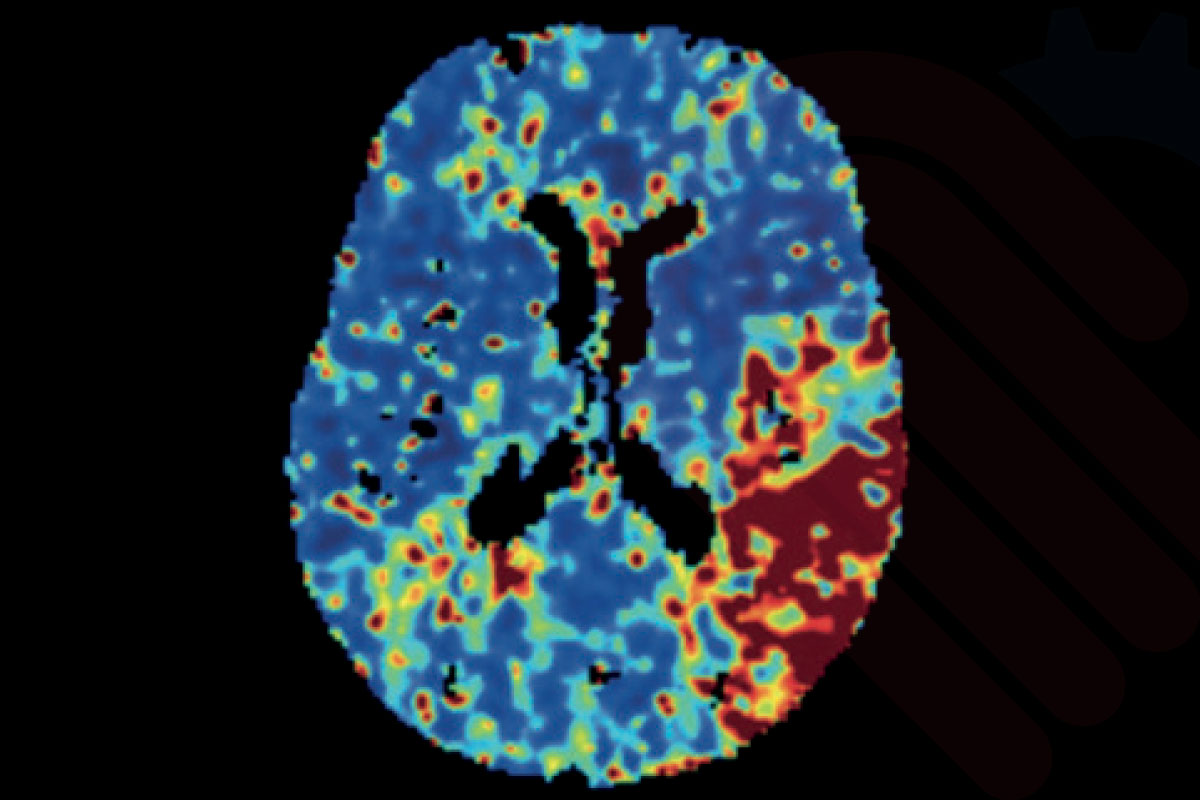

Beyin görüntülemelerinde AI destekli analiz ve raporlama çözümleri, görüntü verilerinin hızlı ve tutarlı şekilde değerlendirilmesine yardımcı olur. Bu yaklaşım, klinik karar destek süreçlerini güçlendirerek zaman kritik hasta yönetimine katkı sağlar.